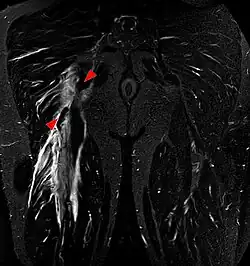

Imaging the hamstring muscles is usually performed with an ultrasound and/or MRI.[9] The biceps femoris is most commonly injured, followed by semitendinosus. Semimembranosus injury is rare. Imaging is useful in differentiating the grade of strain, especially if the muscle is completely torn.[10] In this setting, the level and degree of retraction can be determined, serving as a useful roadmap prior to any surgery. Those with a hamstring strain of greater than 60 mm (2.4 in) in length have a greater risk of recurrence.[11]